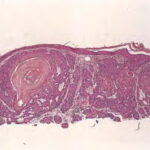

Keratinizing basal cell carcinoma = الورم الفاعدي الخلايا المتقرن

Nodular BCCs account for half of all BCCs and are characterized by nodules of large basophilic cells and stromal retraction . The term micronodular BCC is used to describe tumors with multiple microscopic nodules smaller than 15µm .

Morpheaform or infiltrative BCC consists of strands of tumor cells embedded within a dense fibrous stroma . Tumor cells are closely packed and, in some cases, only one cell thick. Strands of tumor extend deeply into the dermis. The cancer is often larger than the clinical appearance indicates. Recurrent BCC may also demonstrate infiltrating bands and nests of cancer cells embedded within the fibrous stroma of scar.